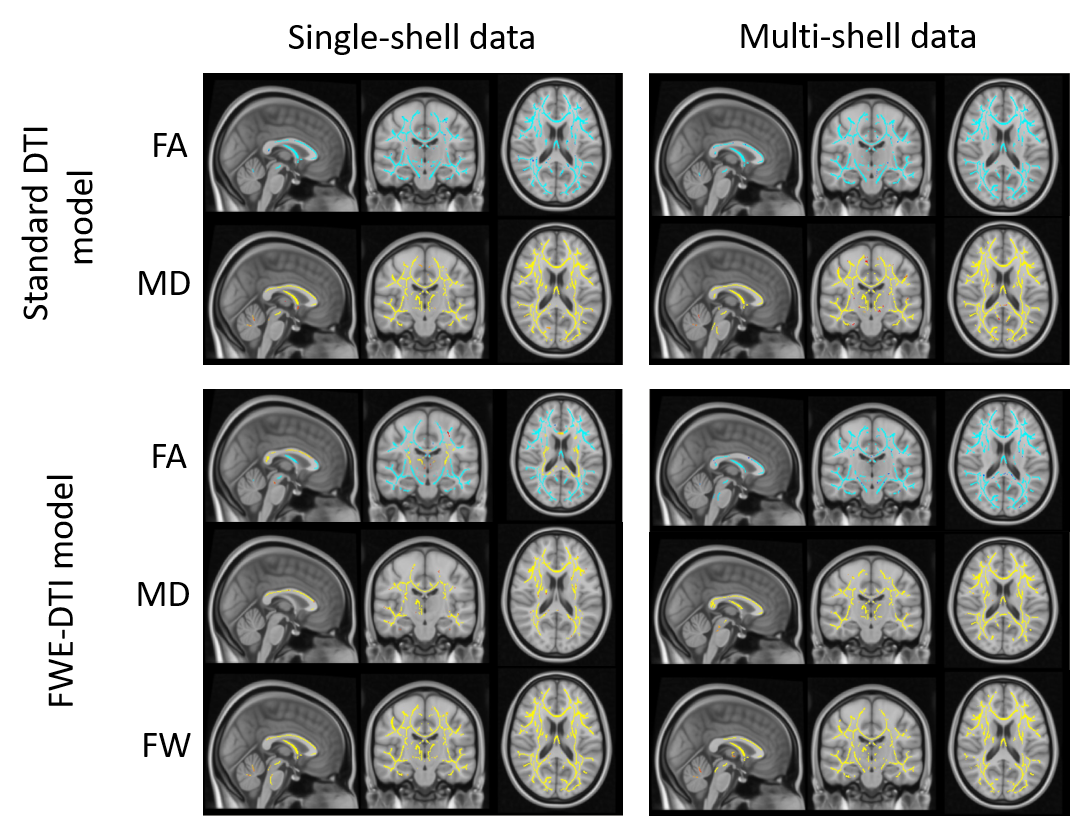

As previously reported4, we found positive and widespread correlations between MD and age, for all combinations of model fitting and dataset (Figure 1). When FWE is performed, the number of significant voxels decreases and this effect is more pronounced for the RGD method (Figure 2B). The FW index also shows widespread negative correlations with age, for both the RGD and NLS algorithms (Figure 1), but more significant voxels were identified with the RGD approach (Figure 2C). Both DTI-based FA metrics produced similar results, showing strong negative correlations with age across the whole brain. However, FW compensated FA maps produced strikingly different results depending on the method employed: the maps obtained with RGD SS identified some brain areas with a strong positive association with age – contrasting the known prevalence of FA decline with age14 – while no such positive correlations were found with MS NLS (Figure 1).

Figure 1 – The effect of FWE elimination on DTI metrics. The results for MD and FW index are consistent for both FWE algorithms, showing widespread negative correlations with age (in blue). However, the FW-compensated FA maps obtained with single-shell FWE modelling resulted in positive correlations with age in some brain regions (in yellow), which could not be replicated when the multi-shell FWE model was used. These were also not present for standard DTI FA maps.